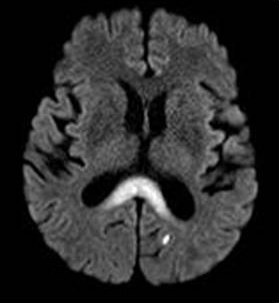

ГМ. Маркиафавы-Биньями болезнь. +

Маркиафавы-Биньями болезнь

Marchiafava, 1897, Bignami, 1903 – редко встречающийся вариант алкогольной энцефалопатии с патологистологичнски проявляющимся поражением (некрозом) мозолистого тела, образованием полостей в ткани мозга и развитием внутренней гидроцефалией. Клинически активная фаза заболевания длится от 2 до 6 лет, завершается она формированием глубокого слабоумия. В психотической стадии болезни наблюдаются слуховые и зрительные галлюцинации, апатия, депрессия, припадки, состояния возбуждения, спутанность сознания, картины псевдопаралича, а также разнообразные неврологические симптомы (тремор рук, дизартрия, абазия, арефлексия или гиперрефлексия, ослабление зрачковых реакций, изменение формы и величины зрачков и мн.др.). Лечение симптоматическое. Синонимы: Дегенерация мозолистого тела, Прогрессирующая алкогольная деменция